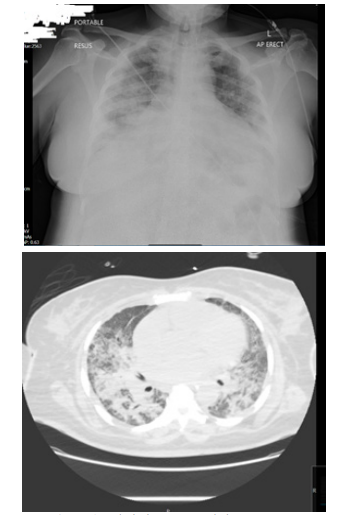

Her chest x-ray was consistent with COVID-19 pneumonia

Figure 1: Admission CXR and chest CT scan.